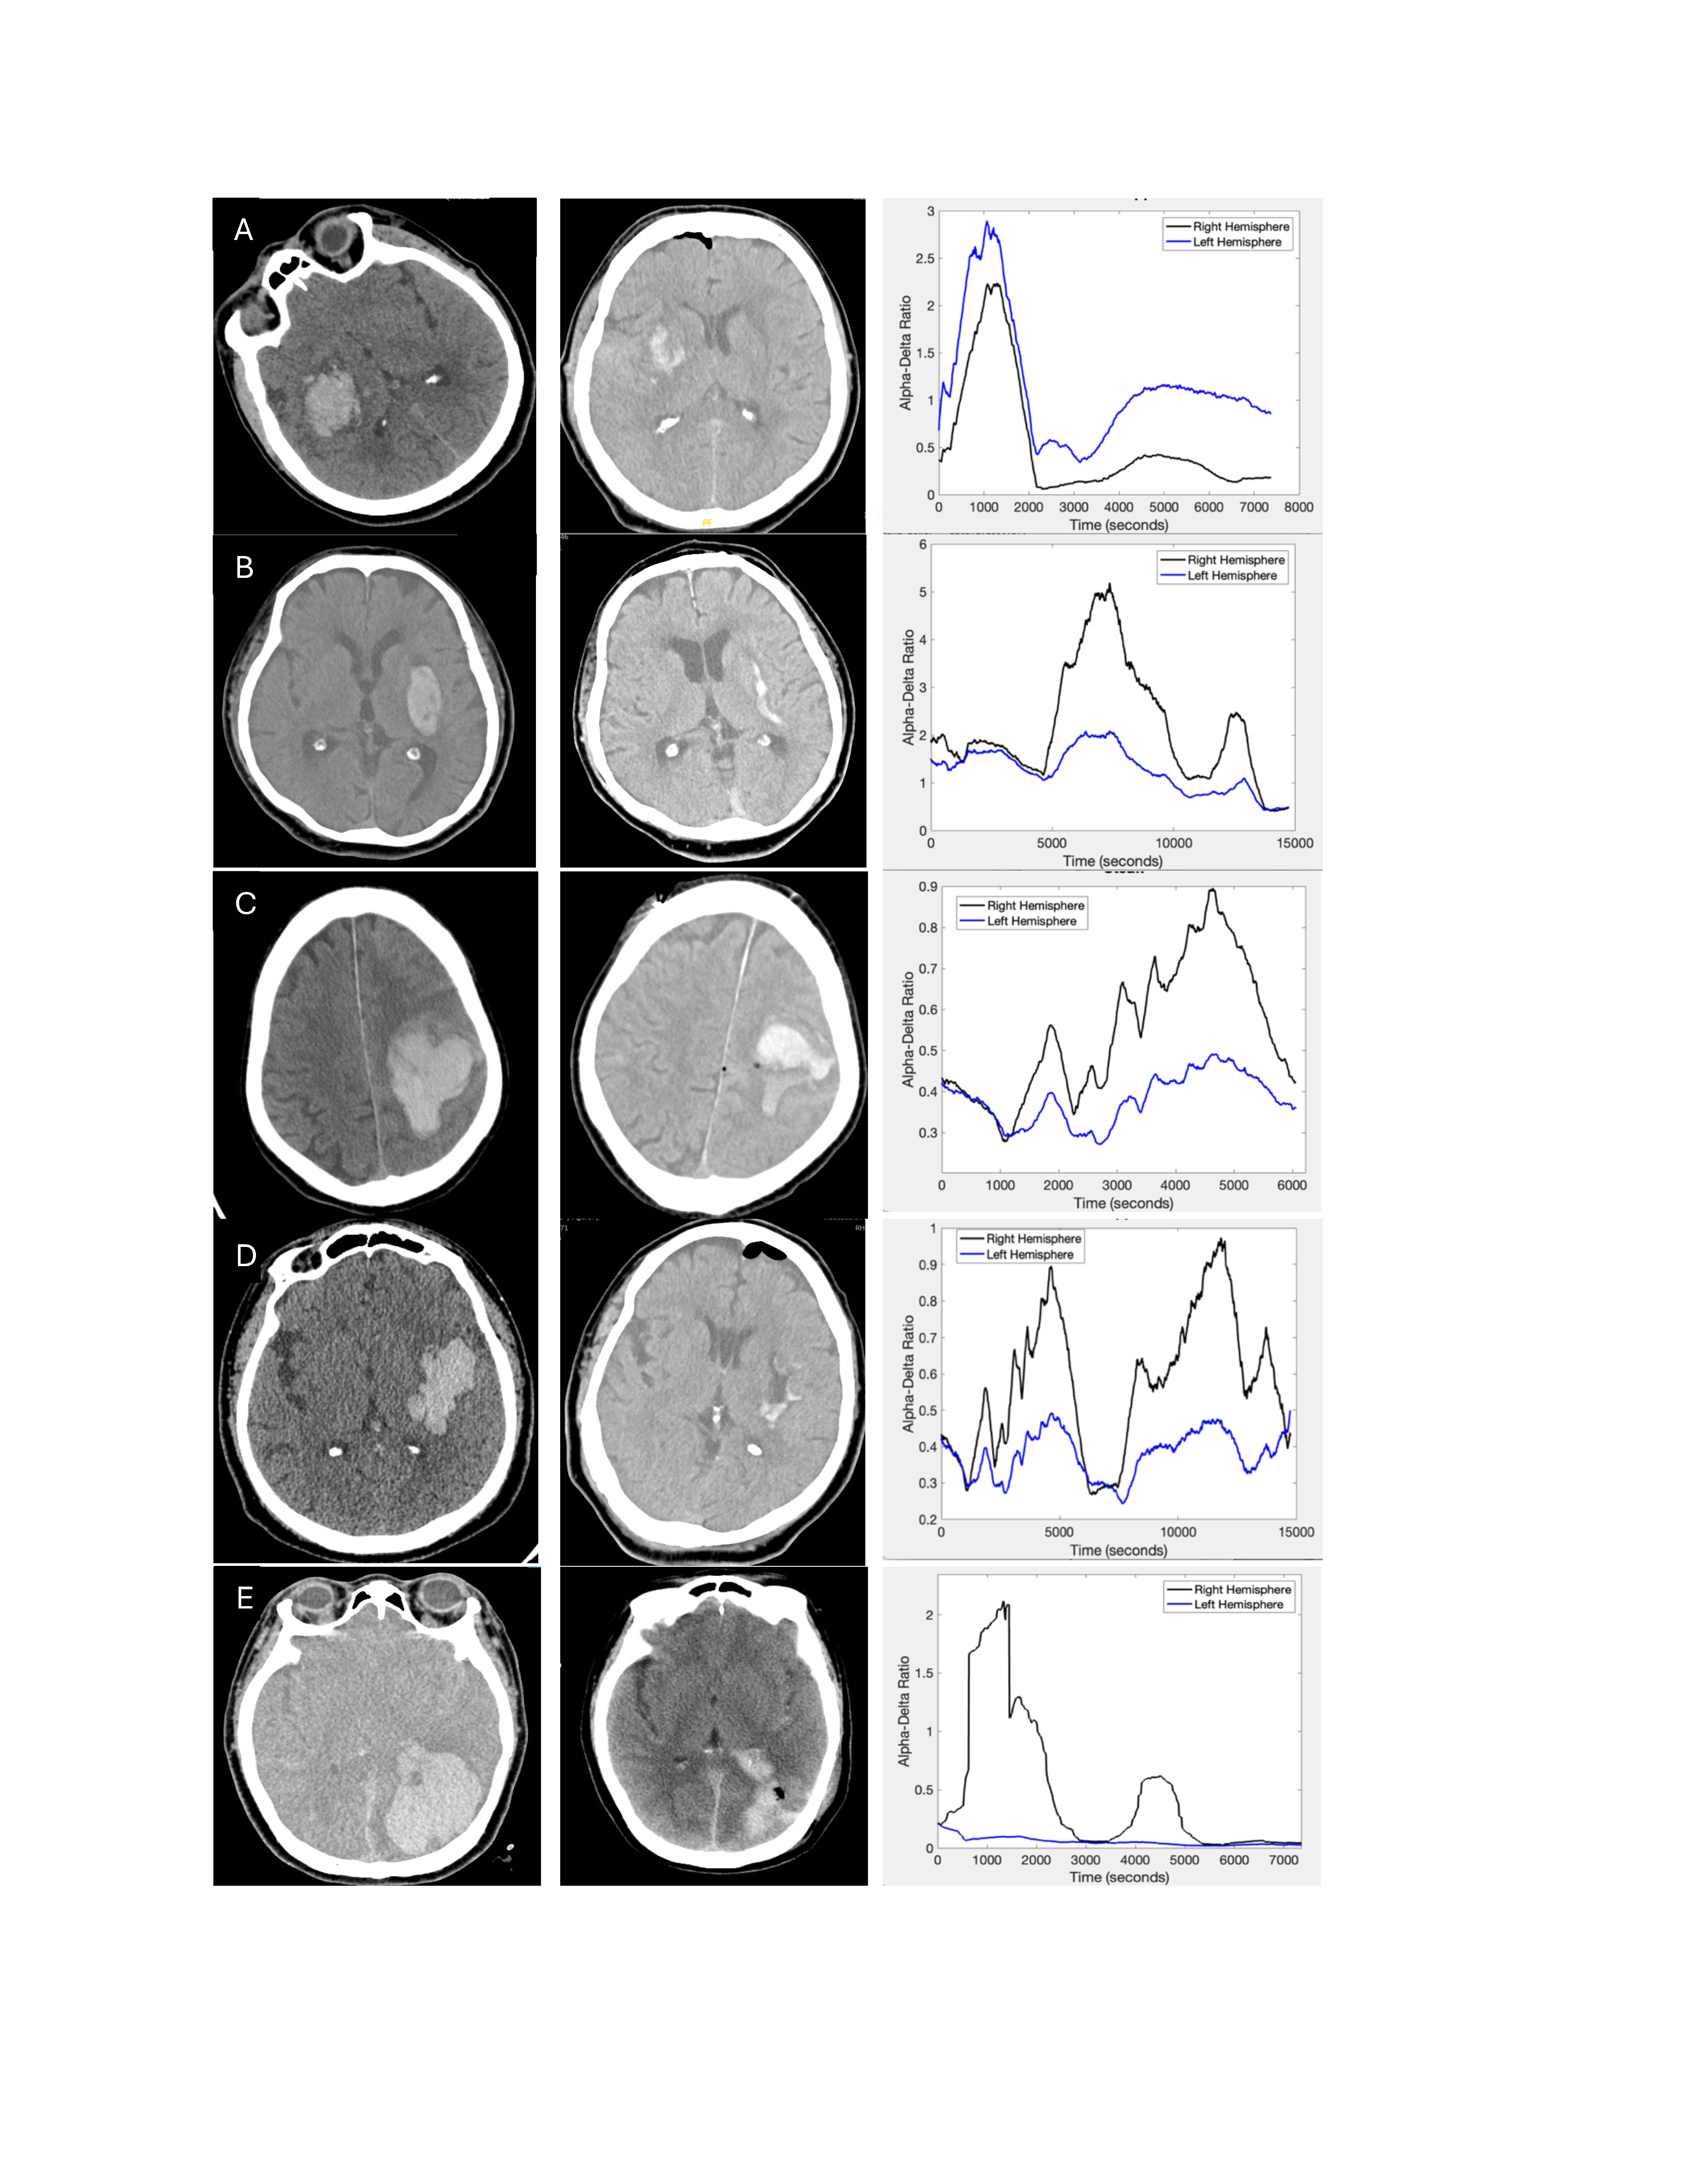

Six patients with ICH who underwent minimally-invasive surgical evacuation were implanted with sub-galeal EEG intraoperatively. Patient age was on average 66.0±7.5 years, National Institutes of Health Stroke Scale at presentation was 19.6±4.0, and ICH volume was 54.0±42.4mL. In five patients, significant reductions in alpha-delta power ratio (power between 8-13Hz relative to power from 2-4Hz) were seen in the hemorrhagic hemisphere compared to the non-hemorrhagic hemisphere. Decreased alpha-delta ratio was seen both with lobar cortical ICH and with basal ganglia ICH. In one of the six patients, higher alpha-delta ratio was seen on the side of left-sided hemorrhage in the context of bilateral epileptiform Lateralized Rhythmic Delta Activity (LRDA) unique to this patient.

In patients at elevated risk of ICH or with ICH, sub-galeal EEG may be an effective method of continuous brain monitoring. In addition to ischemic stroke, decreased alpha-delta ratio on EEG may be seen in hemorrhagic stroke.